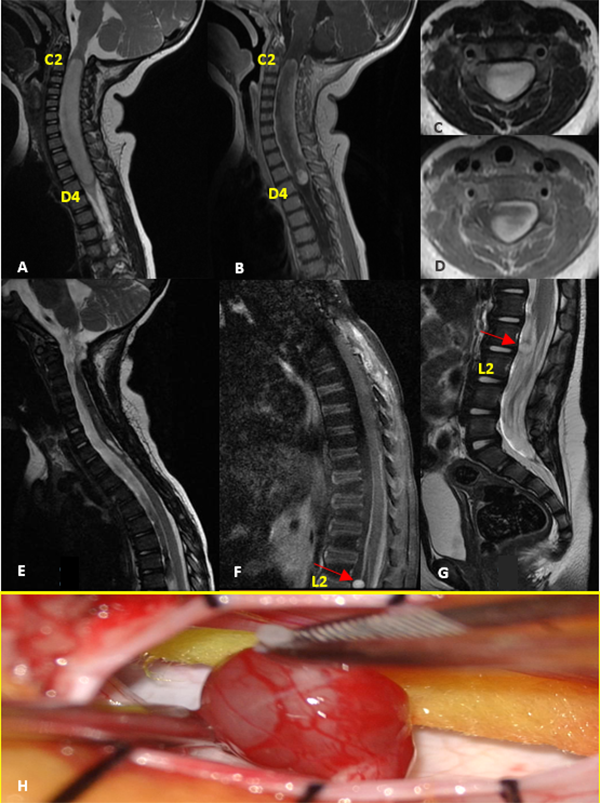

IV: Glioma Difuso de Bajo Grado

Paciente sexo femenino que a los 9 meses se le realizó exéresis total de tumor intramedular cervico-dorsal (C1-D4) en otra institución, cuyo diagnóstico anatomopatológico informó ependimoma de alto grado, por lo que completó tratamiento adyuvante con quimioterapia (6 ciclos de cisplatino, etopósido, vincristina y ciclofosfamida según protocolo HeadStart II), con posterior trasplante autólogo de médula ósea. Inicialmente debutó con falta de adquisición en las pautas motoras asociado a paresia de miembros superiores. En el postoperatorio evolucionó con cuadriparesia e hidrocefalia requiriendo colocación de shunt ventrículo peritoneal. A los 2 años de vida en los controles de RM se evidencia marcado refuerzo postcontraste y engrosamiento de las raíces de la cauda equina, destacándose a la altura de L2, una imagen nodular con intensa captación de contraste, que medía 6 x 5 x 6 mm aproximadamente. Se realizó la resección completa de la lesión. La anatomía patológica reveló glioma difuso de bajo grado (Grado II de la OMS) (Figura 4).

Figura 4:

Glioma Difuso de Bajo Grado. A-D: RM prequirúrgica T1 con contraste y T2 cortes axiales y sagitales. E-G: RM postquirúrgica alejada que evidencia resección completa de tumor cervical con lesión metastásica nodular a nivel de L2 (flecha roja). H: Imagen intraoperatoria de la lesión.